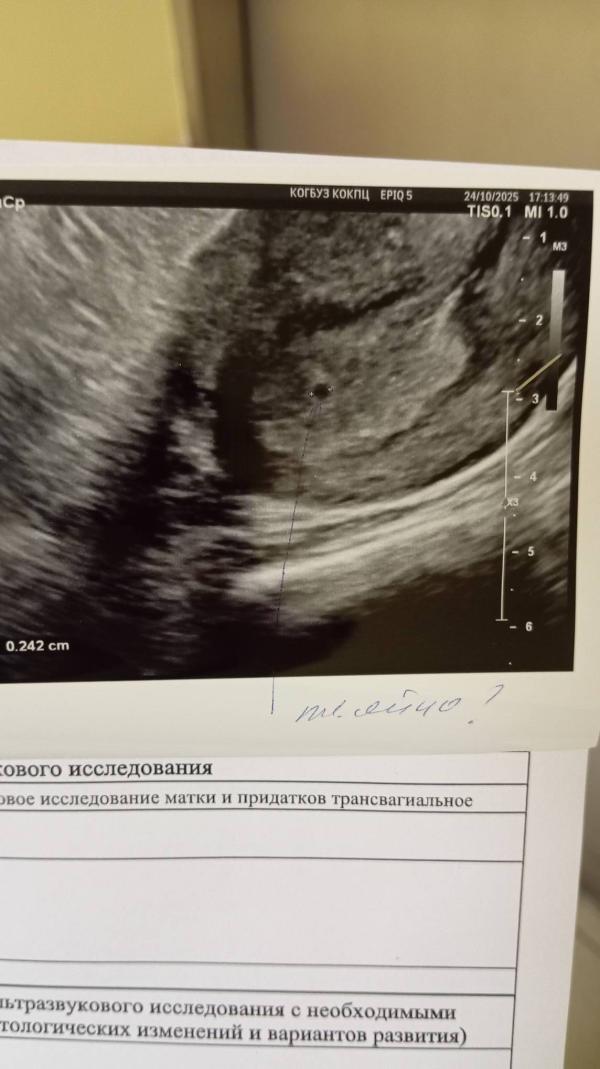

Нашли плодное яйцо в матке: возможная беременность

Нашли в матке плодное яйцо... Типа под вопросом но узистка наша сказала что это оно. Пригласила на УЗИ 29/10.

Кажется у нас будет третий ребенок.

Сто процентов маточная.

У меня такая же крошка была, 3.2мм)